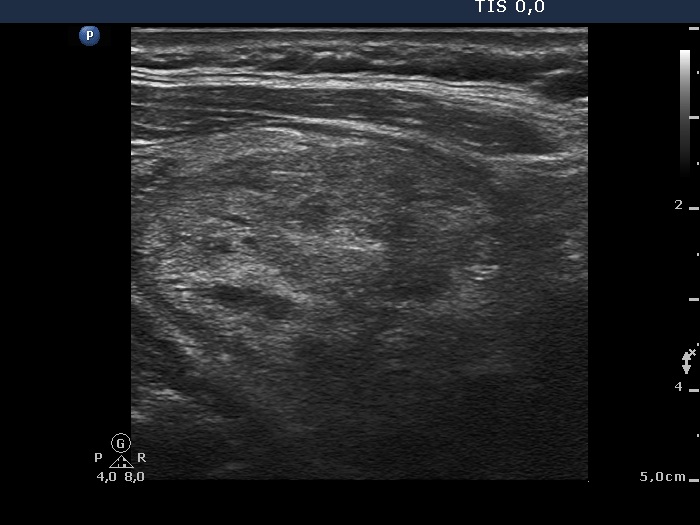

Ultrasonography: a large lesion composed of multiple moderately hypoechogenic and hyperechogenic nodules occupies almost the entire right lobe. There was a small hypoechogenic nodule in the upper pole while a cystic nodule in the central part of the left lobe. The former presented coarse and microcalcifications, too. The vascularization was not specific.